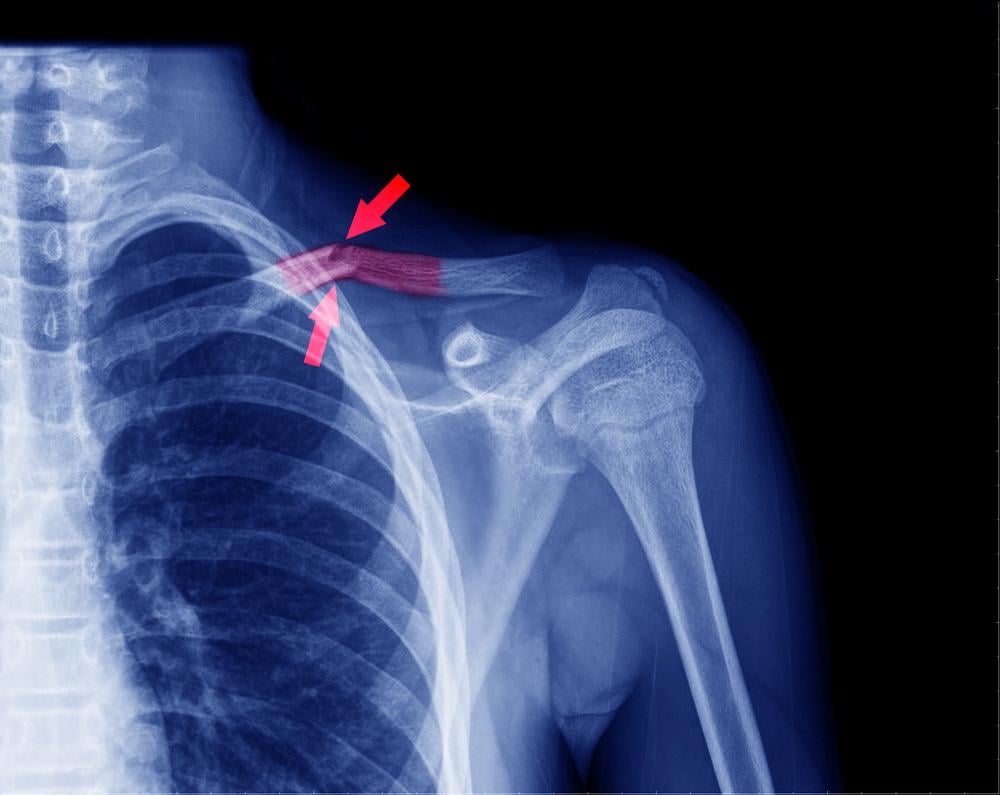

Nếu có nghi ngờ rằng xương đòn của bạn bị gãy, các bác sĩ sẽ khuyên bạn nên chụp X-quang vai để chẩn đoán thêm. X-quang có thể hiển thị hình ảnh của xương đòn bị gãy và mức độ nghiêm trọng của nó hoặc xương khác có bị gãy hay không. Trong một số trường hợp, nếu các bác sĩ cần phải xem xét các vết nứt một cách chi tiết hơn, họ sẽ áp dụng chụp cắt lớp vi tính (CT scan).